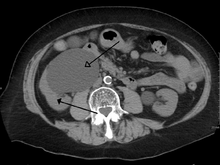

Imaging studies, such as an intravenous urogram (IVU), ultrasound, CT or MRI, are also important investigations in determining the presence and/ or cause of hydronephrosis. Whilst ultrasound allows for visualisation of the ureters and kidneys (and determine the presence of hydronephrosis and / or hydroureter), an IVU is useful for assessing the anatomical location of the obstruction. Antegrade or retrograde pyelography will show similar findings to an IVU but offer a therapeutic option as well. Real-time ultrasounds and color-flow Doppler tests in association with vascular resistance testing helps determine how a given obstruction is effecting urinary functionality in hydronephrotic patients.[12]

The choice of imaging depends on the clinical presentation (history, symptoms and examination findings). In the case of renal colic (one sided loin pain usually accompanied by a trace of blood in the urine) the initial investigation is usually a spiral or helical CT scan. This has the advantage of showing whether there is any obstruction of flow of urine causing hydronephrosis as well as demonstrating the function of the other kidney. Many stones are not visible on plain X-ray or IVU but 99% of stones are visible on CT and therefore CT is becoming a common choice of initial investigation. CT is not used however, when there is a reason to avoid radiation exposure, e.g. in pregnancy.